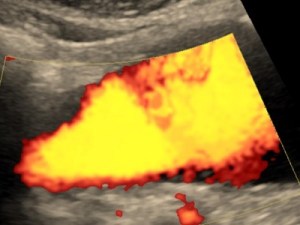

Doppler aorty i tętnic biodrowych lub trzewnych

Badanie wykonywane w celu oceny tętniaków i zwężeń w tętnicach brzucha. Do badania trzeba być około 4-6 godz. na czczo i przyjmować 1 dzień wcześniej Espumisan.

Tętniak aorty brzusznej.